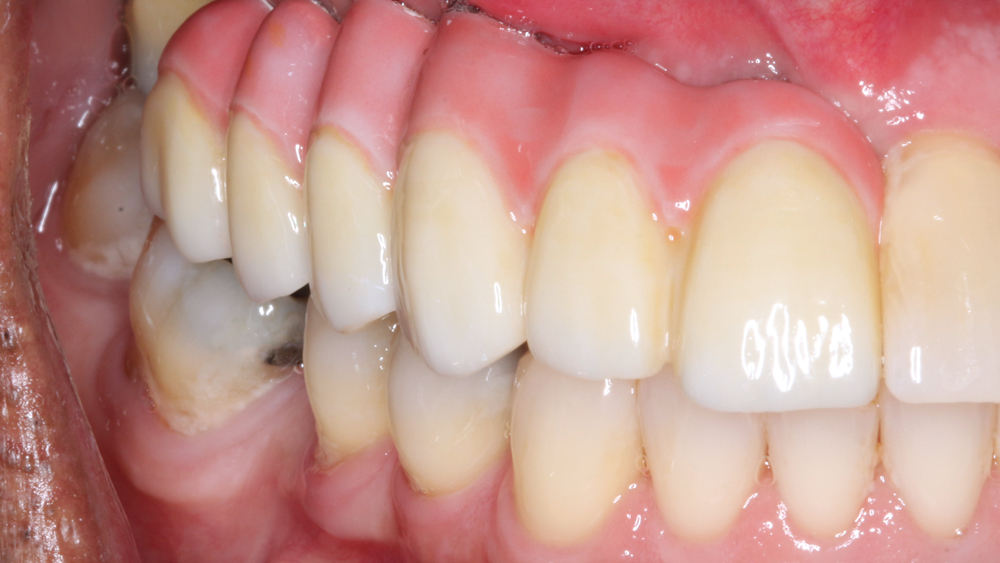

The chief complaint from my patient, Weldon, was missing teeth and gaps between his teeth. The preoperative evaluation showed periodontally involved and non-restorable maxillary right teeth #2–8 and significant periodontal bone loss, which would need to be addressed. The periodontal condition was stable in the patient’s left maxilla, and he was satisfied with the existing esthetics in that quadrant.

There was significant bone loss on the right side of the maxilla, from the existing non-restorable central incisor back to the second molar. With this bone loss and mobility of the teeth, there was vertical and horizontal deficiency of the available bone. Options considered included an autogenous block graft to attempt to increase bone height and width. The second option was to work with the available bone, extract the non-restorable teeth on the right side of the maxillary arch, immediately place implants, and create esthetics with a longer prosthesis that includes pink-colored gingival areas. A BruxZir Solid Zirconia implant bridge was the optimal long-term solution because the entire prosthesis, including the gingival areas, is milled from a single block of high-strength solid zirconia, affording unmatched durability for this type of restoration. Although Weldon did not have a high smile line, he was attracted to a prosthetic design that included gingival areas to restore esthetics where tissue loss had occurred.

RESTORATIVE TECHNIQUES FOR ESTHETICS AND OCCLUSION

Esthetics and occlusion can be challenging in these types of cases. Restoring half an arch and trying to mirror the contralateral soft tissue and dentition with proper contours and shade requires patience and resolve. The lab provided a PMMA try-in prosthesis, which I evaluated with Weldon. The try-in allowed us to easily resolve any discrepancies with the prosthetic design and develop ideal occlusion. Once Weldon agreed on the esthetics, the PMMA provisional was returned to the lab and duplicated in BruxZir Solid Zirconia. This extra step eliminates excessive chairside adjustments upon seating of the final prosthesis.

BruxZir Solid Zirconia has proven to be extremely strong yet compatible with opposing natural dentition; the material exhibits minimal wear on the opposing enamel. Its color and shading are extremely natural in appearance, and I have no concerns about chipping or cracking of the material over time. The final seating of the prosthesis was straightforward, and I have confidence that the material is a long-lasting solution. Weldon was thrilled with the final restoration, as we were able to surpass his expectations and provide him with a fixed, functional, esthetic result.

Understanding the foundation required to predictably place dental implants, including effective extraction techniques, socket management and grafting procedures, has improved the prognosis. Working with talented and well-trained laboratory technicians helps us plan the final prosthetic result prior to any surgical procedure. Innovative laboratory techniques and materials provide outstanding functional and esthetic results. As for Weldon, his BruxZir implant bridge ensures an excellent long-term prognosis as well as restored esthetics in an area that was compromised by tissue loss prior to treatment.